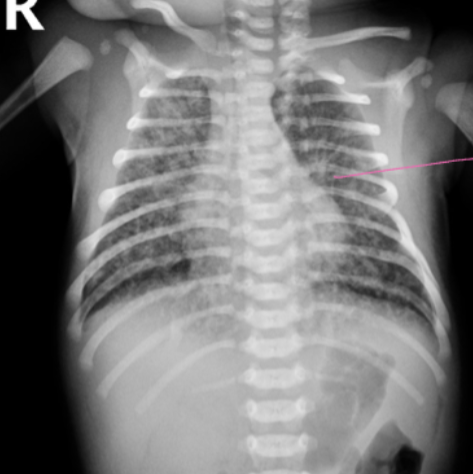

MECONIUM ASPIRATION:

- Hyperinflation, Consolidation, Patchy infiltrates

- If severe, air leak and pneumomediastinum may occur